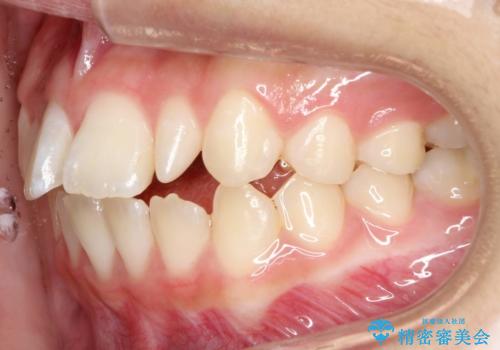

上あごの2番目の歯は矮小歯といって、生まれつき小さい歯となる事がよくあります。

このような場合、矯正によりスペースを集め、本来あるべき形態にセラミックで修正することもできます。